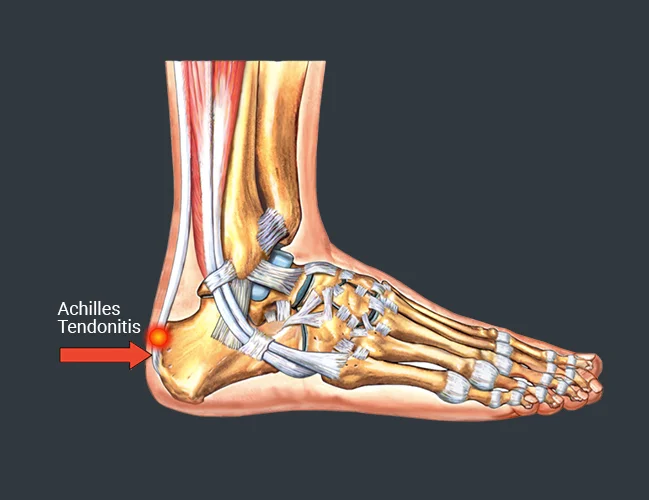

Common Conditions Causing Heel Pain

Heel Pain Causes Diagnosis Treatment

A Stabbing Heel Pain